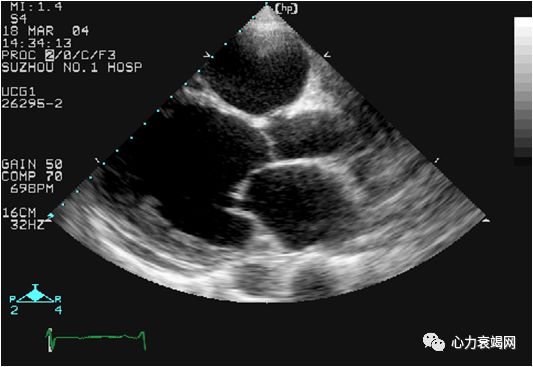

➤ ECHO

DCM的特点:腔大、壁薄、口小、收缩功能下降